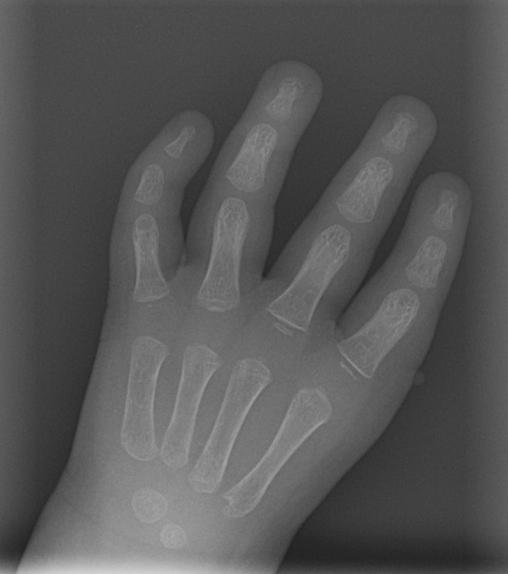

Connor Woodle's hand prior to surgery

Thumb aplasia is a rare congenital defect — occurring in one out of every 100,000 births — in which a child is missing one or both thumbs. Because the condition is so uncommon, few surgeons get an opportunity to develop the advanced skills required to treat it effectively. In his career as an orthopaedic surgeon specializing in congenital hand abnormalities, Bobby Chhabra, MD, chair of the UVA Department of Orthopaedic Surgery, has treated more than a dozen of these young patients.

One of the more challenging patients with thumb aplasia Chhabra has treated, Connor Woodle was referred to UVA Hand Center at just two weeks of age. He was missing not one, but both of his thumbs.